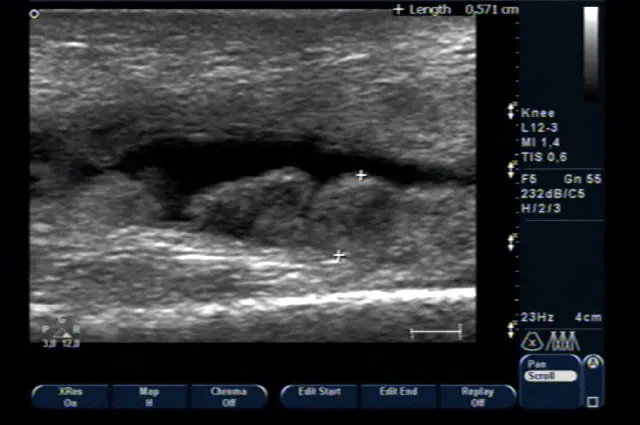

Приклад ураження суглоба при ревматоїдному артриті. Можна бачити проліферацію (розростання) синовіальної оболонки суглоба.

- УЗД суглобів дозволяє встановити ревматологічний діагноз за станом синовіальної оболонки суглоба. Наявність розростання синовії (проліферації) – 100% ознака його ревматичного ураження (фото нижче).